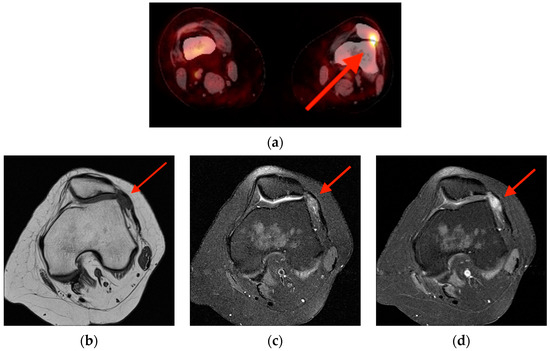

4.1. Tenosynovial Giant Cell Tumor/Pigmented Villonodular Synovitis

- Broski, S.M.; Murdoch, N.M.; Skinner, J.A.; Wenger, D.E. Pigmented Villonodular Synovitis: Potential Pitfall on Oncologic 18F-FDG PET/CT. Clin. Nucl. Med. 2016, 41, e24–e31. [Google Scholar] [CrossRef] [PubMed]

- Kitapci, M.T.; Coleman, R.E. Incidental detection of pigmented villonodular synovitis on FDG PET. Clin. Nucl. Med. 2003, 28, 668–669. [Google Scholar] [CrossRef] [PubMed]

- Hughes, T.H.; Sartoris, D.J.; Schweitzer, M.E.; Resnick, D.L. Pigmented villonodular synovitis: MRI characteristics. Skelet. Radiol. 1995, 24, 7–12. [Google Scholar] [CrossRef]

- Cohen-Levy, W.B.; Pretell-Mazzini, J.; Singer, A.D.; Subhawong, T.; Greif, D.N.; Jose, J. Significance of incidental intra-articular and peri-articular FDG avid foci on PET/CT. Acta Radiol. 2019, 60, 78–84. [Google Scholar] [CrossRef] [PubMed]